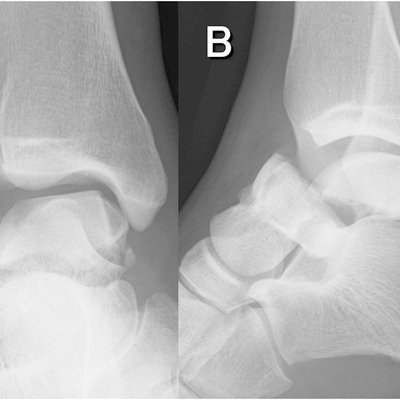

Click on an image below to view more info.